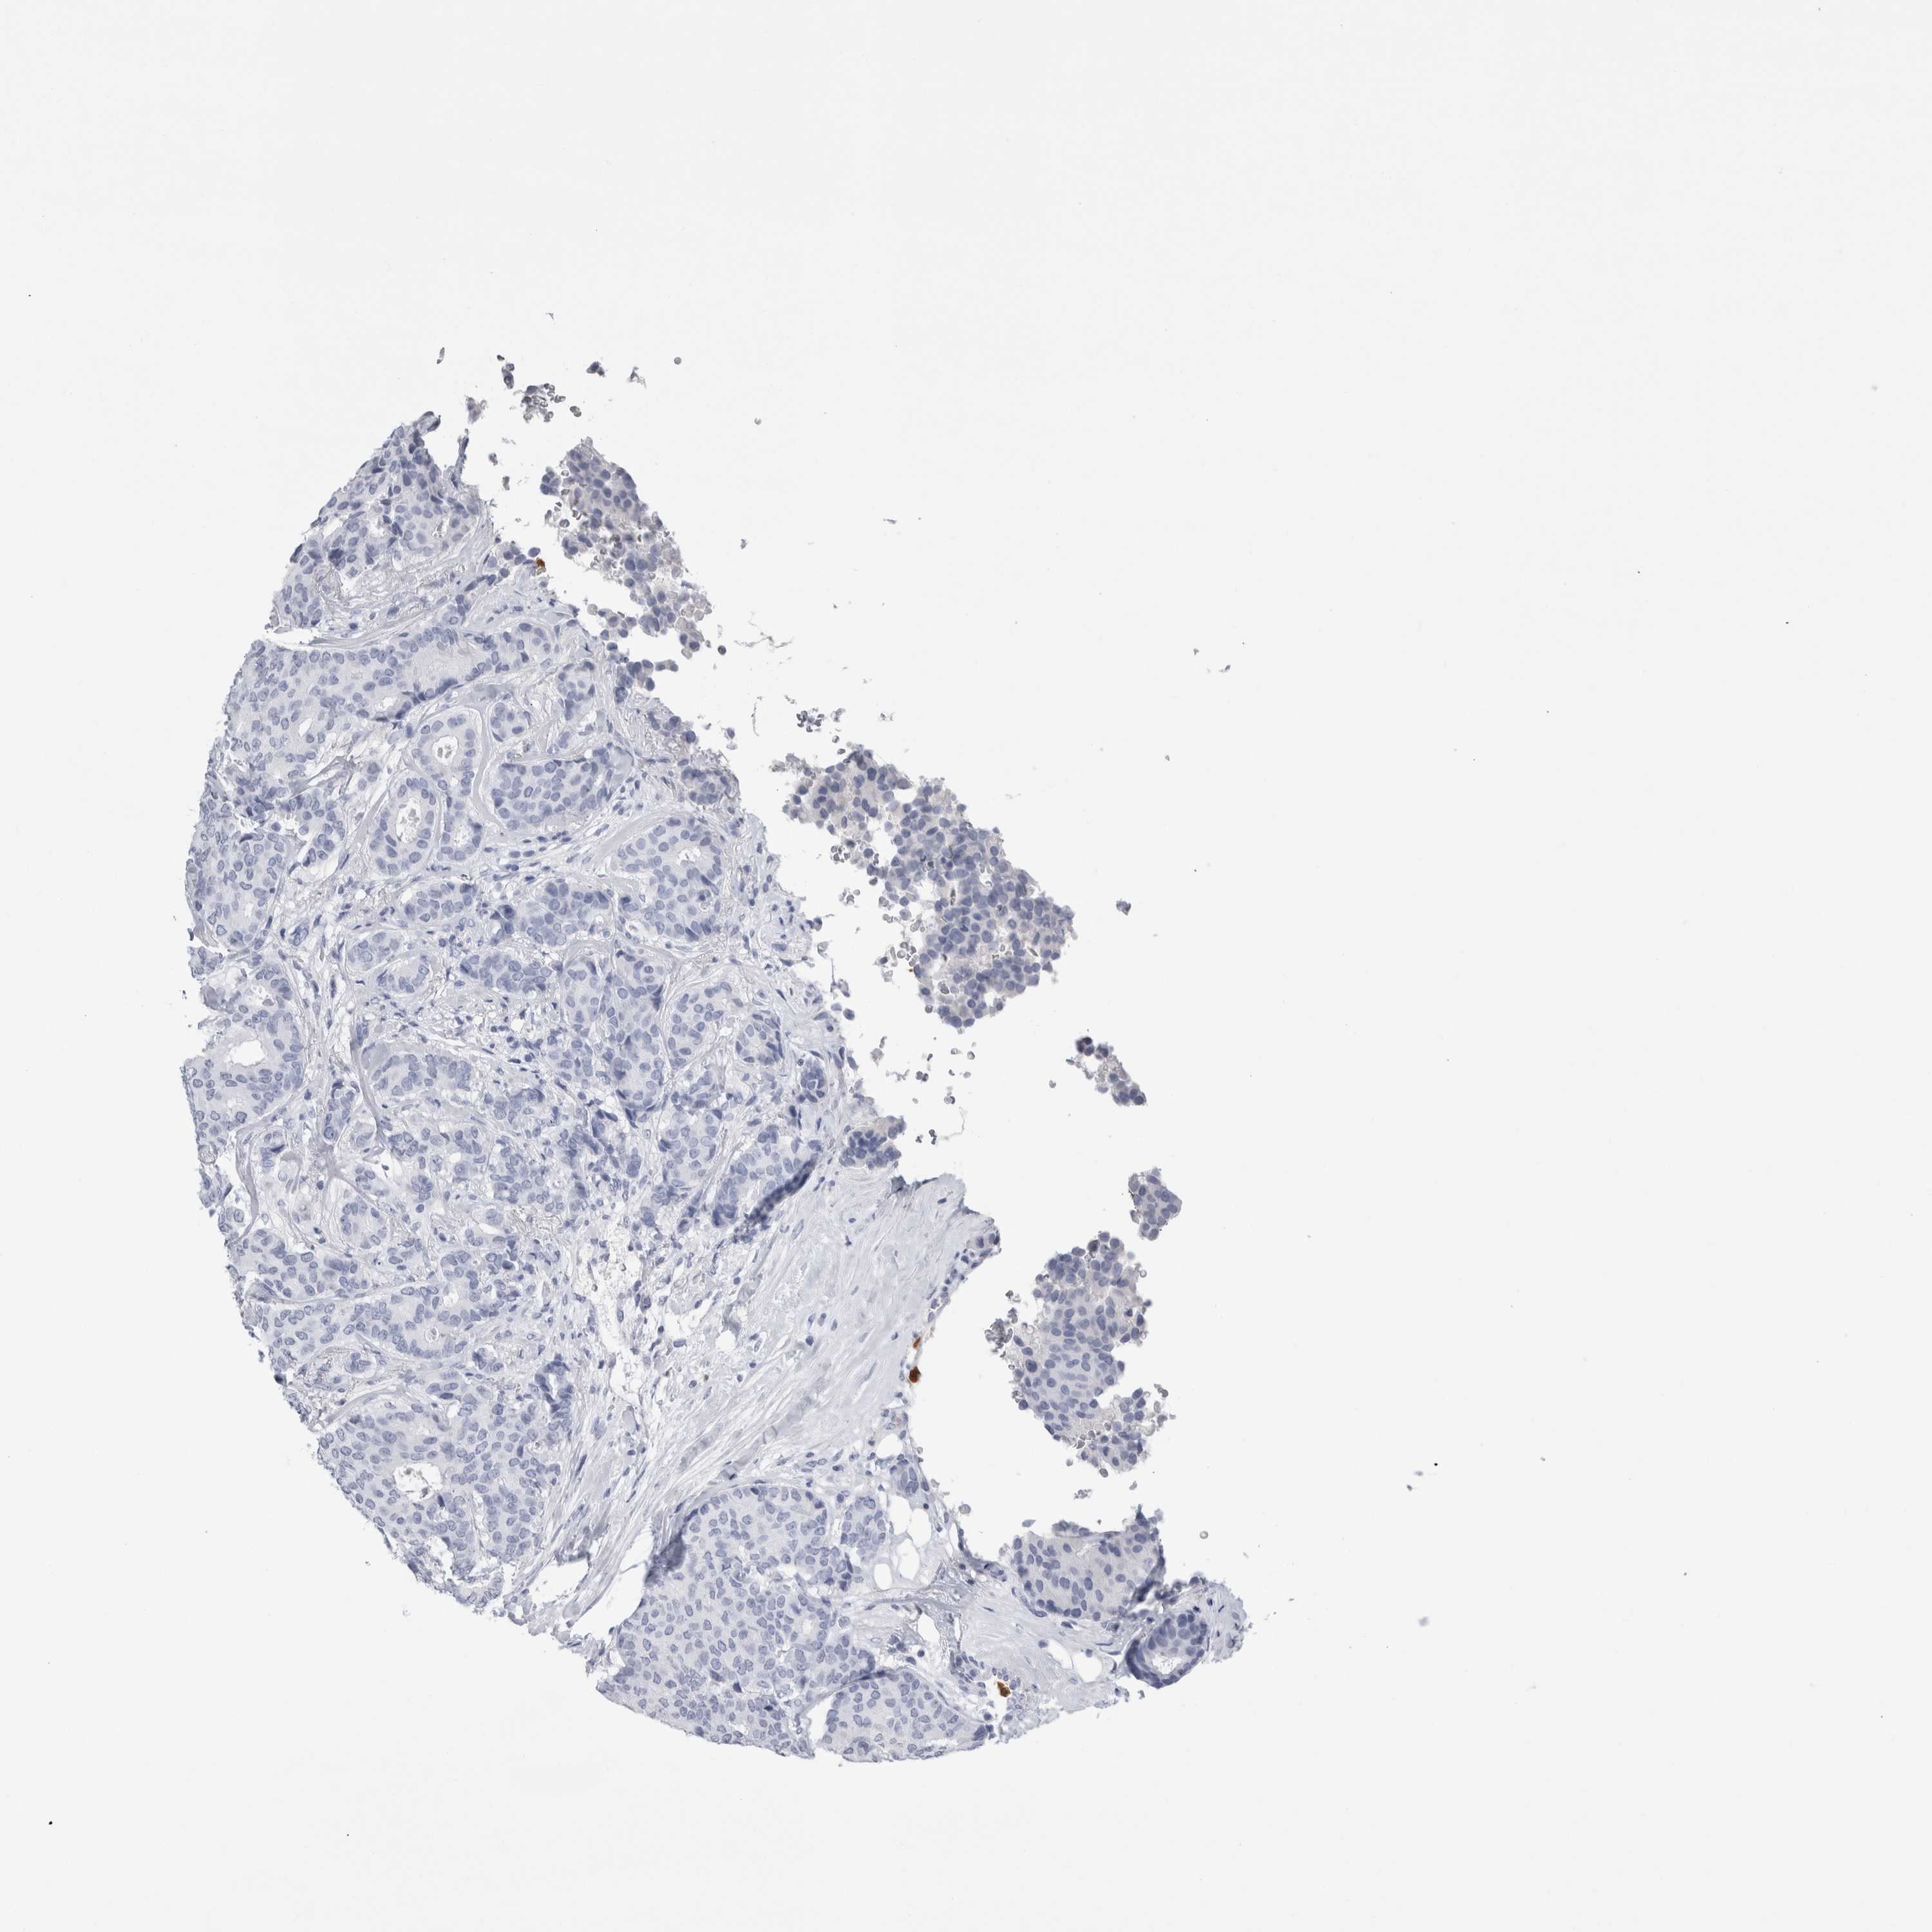

CANCER BREAST CANCER Show tissue menu

BRCA TCGA BRCA VALIDATION PROTEIN EXPRESSION